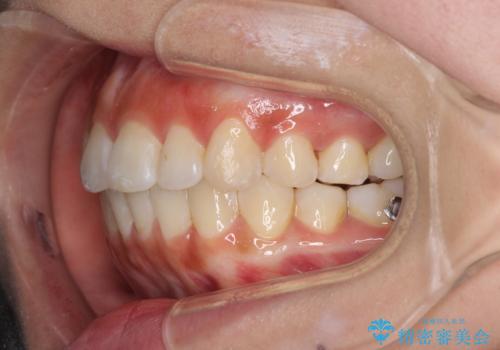

前歯のデコボコが気になる インビザラインによる矯正治療

- 上下前歯のデコボコを気にして来院された患者様です。

インビザラインによる上下歯列の拡大と、IPR(歯と歯の間を削る)にるスペースの獲得により、前歯のデコボコを改善することとしました。

しっかりと装着時間を遵守してくださったので、思い通りの歯列に整えることができました。

結婚式前に終了させることができ、患者様には大変満足していただきました。